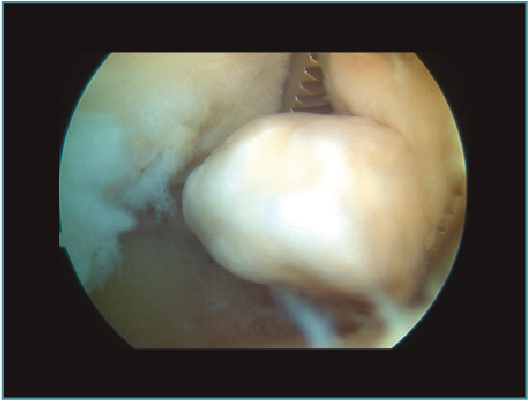

La pared anterior corresponde a la cara posterior del húmero distal, incluyendo la fosa olecraneana y la porción articular posterior de la tróclea humeral (Figura 17). En la fosa olecraneana es característica la localización de cuerpos libres o proliferaciones osteocondrales que bloquean o limitan la extensión del codo al generar un compromiso con la punta del olécranon. En el cuadro de impingement posteromedial de codo es característico el hallazgo de lesión osteocondral en la zona medial del olécranon y la tróclea, presencia de cuerpos libres (Figura 18) y proliferación ósea en la punta del olécranon(12).

Figura 8. Cuerpos libres (A y B) en compartimento anterior. Codo derecho, visión con óptica de 30° desde portal medial.

Figura 18. Suelo del compartimento posterior con cuerpo libre en fosa olecraneana. En un codo izquierdo. Visión con óptica de 30° desde portal posterolateral.